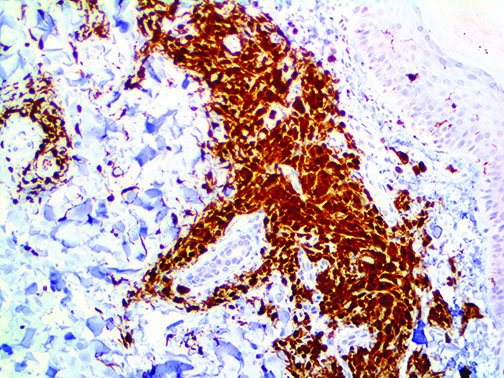

The first cytokines released are interleukin 1β (IL-1β) and tumor necrosis factor-α (TNF-α), which attract a variety of circulating white blood cells (WBCs) to the infection site, including neutrophils, monocytes, macrophages, and natural killer (NK) cells. This response, along with the antipathogenic chemicals released by these cells (i.e., complement), comprise the innate immune response. These cells directly attack the invading pathogen and also release additional cytokines, chief among them interleukin-1 and 6 (IL-6). IL-6 is essential for invoking the adaptive immune response, which calls T-cells, B-cells, and T helper (Th) cells to the infection site. IL-6 also stimulates further recruitment, proliferation and activation of macrophages.

This activation induces inflammatory monocytes to highly express IL-6, starting a localized and then systemic cascade effect that results in hyperproduction of IL-6, which accelerates the inflammatory process. Because IL-6 also increases vascular permeability, excessive levels cause blood vessels to become very leaky. This, along with clotting factors released from vascular endothelial cells, stimulates the coagulation cascade, resulting in microthrombosis (tiny clots), which leads to ischemia and tissue death of the kidney, intestines, heart, liver, brain and extremities.